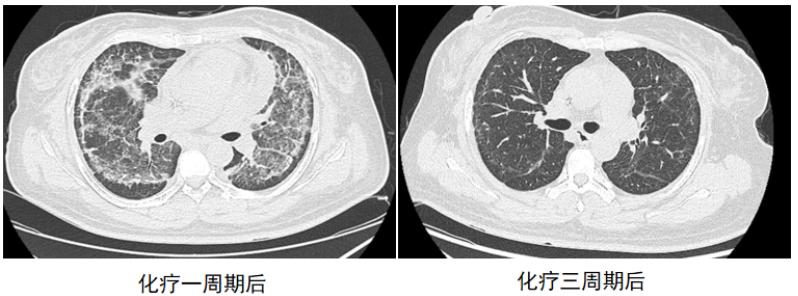

化疗1周期后,CT可见病灶明显吸收,化疗3周期后,胸部CT可见病变基本全部吸收(图2)。后续复查肺部基本恢复正常。

图2  患者化疗一周期和三周期后胸部CT